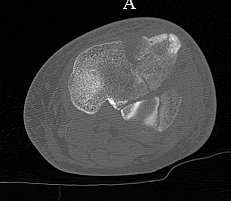

Серия КТ сканов в аппарате

Голень-41-С3.1 - полный внутрисуставной и метафизарный оскольчатый перелом с доминантным повреждением наружного мыщелка, с импрессией центральной части плато. Первичная тактика полный респект по АО и ОТА. на фоне лигаметотаксиса выполнено КТ, которое четко детализирует повреждение и определяет дальнейшую тактику.

Основная проблема не бугристость, а внутрисуставное повреждение латерального мыщелка с импрессией центральной части. С большей вероятностью, есть паракапсуллярное продольное повреждение наружного мениска.